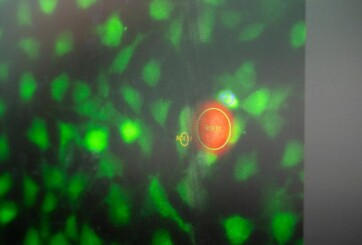

Mikroroboter für die Erforschung von Zellen

Chancen für Krebsbehandlung und Wundheilung. 30 Mikrometer große Roboter stimulieren Zellen Technologische Plattform zur Herstellung der Mikroroboter entwickelt Mechanismen der Ionenkanäle lassen sich beeinflussen Eine Forschendengruppe der Technischen Universität München (TUM) hat weltweit erstmals einen Mikroroboter entwickelt, der im Zellverbund navigieren und einzelne Zellen gezielt stimulieren kann. Die Professorin für Nano- und Mikrorobotik Berna Özkale Edelmann sieht darin das Potenzial, neue Behandlungsmethoden für den Menschen zu finden. Sie sind rund, halb so dick wie ein Haar, enthalten Goldstäbchen und fluoreszierenden…